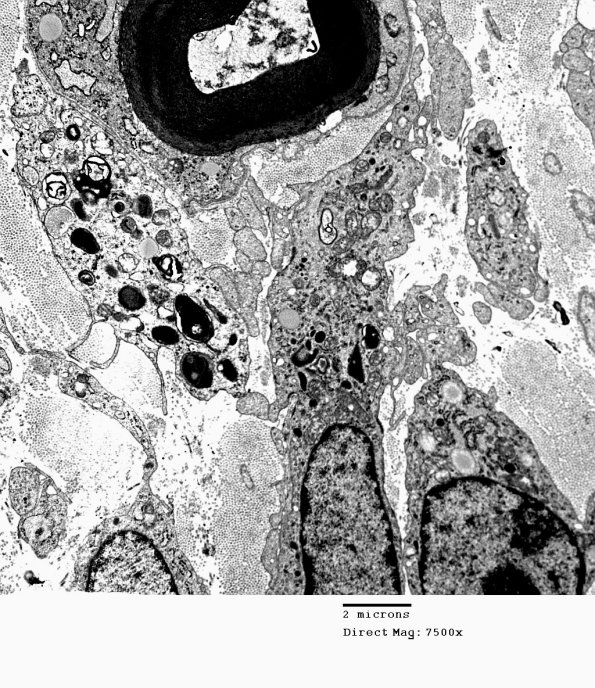

Washington University Experience | PERIPHERAL NEUROPATHY | 4 AXONAL DEGENERATION | 4 Macrophages | 2D2 Axonal Degeneration, granular axoplasm, sarcoid (Case 5) EM 033 - Copy

In this case there are several macrophages contacting a degenerating axon whose myelin remains intact at this stage.